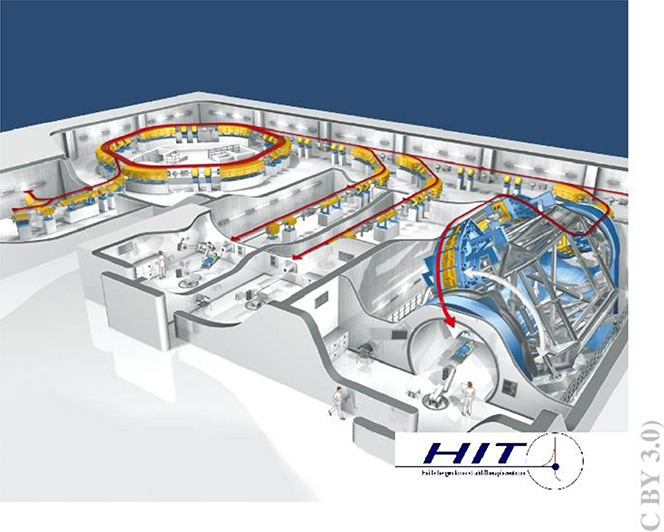

For protons and 3He/4He similar radio-biological properties have been determined, but the lateral scattering is reduced by nearly 50% in the case of helium ions versus protons (figure 5.7). In recent years, helium ions again became of interest for clinical cases where neither protons nor carbon ions are ideally suited, especially for treating paediatric tumours. Currently, patient irradiations with scanned 4He ions at the Heidelberg Ion beam Therapy Center (HIT) in Germany are used only in 'treatment attempts' ('individuelle Heilversuche') and will go into regular operation by mid 2024. Other ion therapy facilities in Europe (e.g., CNAO in Italy and MedAustron in Austria) have also started technical upgrades to produce helium ion beams in the near future.

5.2.2.2. Image-guided hadron therapy using MRI

The observation of the patient's position during treatment has become more and more a standard procedure. 3D camera systems make it possible to control the location of the patient within tenths of millimetres observing the exterior of the body. But organs struck by tumours can move dramatically within the abdomen, which is not visible from outside. To observe the soft tissues an MRI scanner is the preferred diagnostic tool. But due to the moderate to high fields used the charged particle beam is affected. In addition, conventional MRI scanners are not constructed to have an inlet for radiation to be applied in parallel to the diagnostic procedure. Nevertheless, studies like ARTEMIS at HIT in Heidelberg have been started to investigate possible arrangements of open, low-field MRIs (figure 5.8). Still the deflection and/or distortion of the beam can be observed, but algorithms will be developed to cancel out this influence of the MRI's magnetic field. A second goal of such studies is to optimize the design of the measurement coils to spare out space for the beam entrance fields. A further aspect should not be underestimated—the impact of the magnetic (stray) fields on the QA devices and the online monitoring detectors used during treatment. All these have to be examined and possibly adapted to be magnetic field compatible; at worst new or alternative detector principles have to be applied. A lot of technical solutions have to be found in the next years before MRI scanners can be introduced in regular particle beam therapy.

In addition, modern control systems providing the multiple energy extraction method—using several post-accelerations in the same synchrtotron cycle—have to be developed to enhance the duty cycle of such machines. A new approach using time-sensitive networking (TSN), the next generation of (real-time) ethernet in industry, will be implemented at HIT (partly within HITRIplus) in the next years.